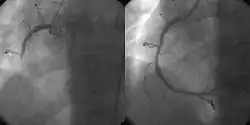

Hyppige sygdomme der behandles er fx åreforkalkning, aneurismer (udposninger af blodkar), blodpropper, iskæmi og lymfødem. Indgreb der udføres i karkirurgien omfatter bl.a. ballonudvidelse og kirurgisk fjernelse af blodpropper (embolektomi).